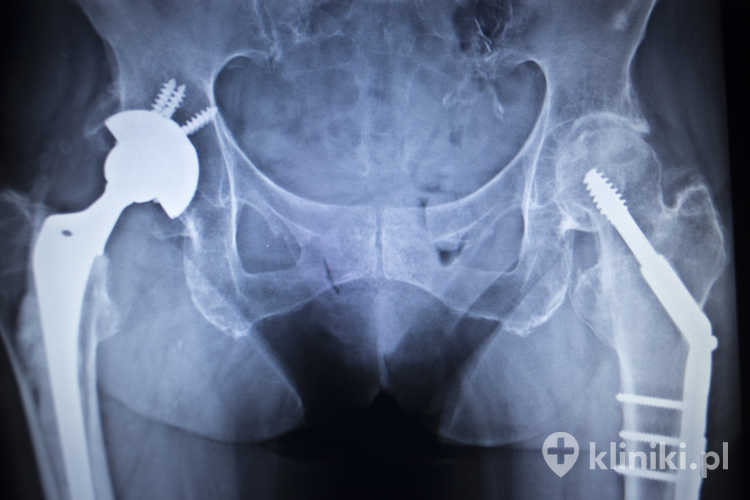

Endoprotezy stawu biodrowego dzielą się pod względem ilości elementów składowych oraz sposobu ich implantacji (wszczepienia) do kości pacjenta. Wyróżniamy zatem endoprotezy połowicze i całkowite, dwu-, trój- i więcej elementowe oraz bipolarne, cementowe, hybrydowe i bezcementowe. Endoprotezy stawu biodrowego różnią się także w zakresie budowy trzpienia i sposobu artykulacji, czyli połączenia stawowego.

Endoprotezy stawu biodrowego to sztuczne konstrukcje, zastępujące zniszczone i nieprawidłowo funkcjonujące elementy składowe stawu. Z tego względu elementy te muszą przypominać w budowie trzon kości udowej, jej głowę oraz panewkę stawu biodrowego. Właściwy dobór wszystkich składowych endoprotezy biodra oraz właściwe ich zamocowanie są warunkiem prawidłowego funkcjonowania stawu i pełnej rehabilitacji.

Pod względem zakresu planowanej lub wykonanej operacji endoprotezy stawu biodrowego dzieli się na połowicze i całkowite. Bardzo ważnym kryterium jest także sposób mocowania poszczególnych elementów ze sobą oraz z pozostałym kośćcem pacjenta.

Endoproteza połowicza (hemiartroplastyka) zastępuje tylko głowę i szyjkę kości udowej przy pozostawieniu własnej panewki. Zwykle stosuje się ją u osób starszych po złamaniu szyjki kości udowej, jeśli chrząstka panewki jest zachowana. Endoproteza całkowita (alloplastyka całkowita, THA) zastępuje zarówno element udowy, jak i panewkę i jest najczęściej wybierana w chorobie zwyrodnieniowej, jałowej martwicy głowy kości udowej, dysplazji lub innych schorzeniach, które obejmują również panewkę.

Endoproteza całkowita stawu biodrowego

Endoprotezy całkowite składają się zazwyczaj z metalowej czaszy panewki osadzanej w kości miednicy (wbijanej lub wkręcanej), wkładki (polietylenowej lub ceramicznej) oraz elementu udowego: trzpienia z wymienną głową. W niektórych rozwiązaniach stosuje się panewki o podwójnej mobilności (dual mobility), w których wkładka polietylenowa jest ruchoma względem czaszy, co może zwiększać stabilność i zmniejszać ryzyko zwichnięcia.